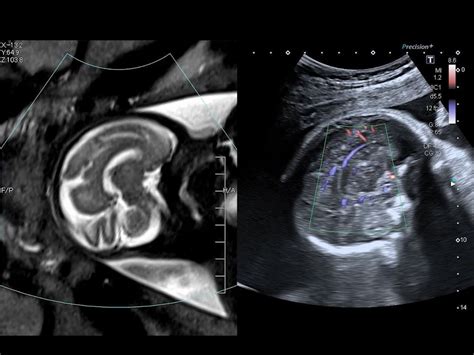

Fusion imaging in ultrasound Ultrasound fusion is an emerging technique in the field of abdominal imaging with translation possibilities to neuroradiology.

• Ultrasound fusion is an emerging technique in the field of abdominal imaging with translation possibilities to neuroradiology. This technique involves the co-registered display of .